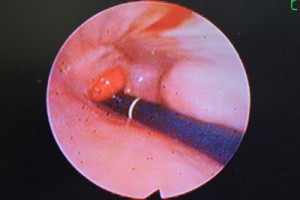

内視鏡検査では噴門(食道と胃の移行部)にサクランボ状の腫瘤が認められた。

腫瘤の他、胃と十二指腸の粘膜をそれぞれ5〜6カ所サンプリングし病理組織検査を行った所、胃腺癌と診断されました。